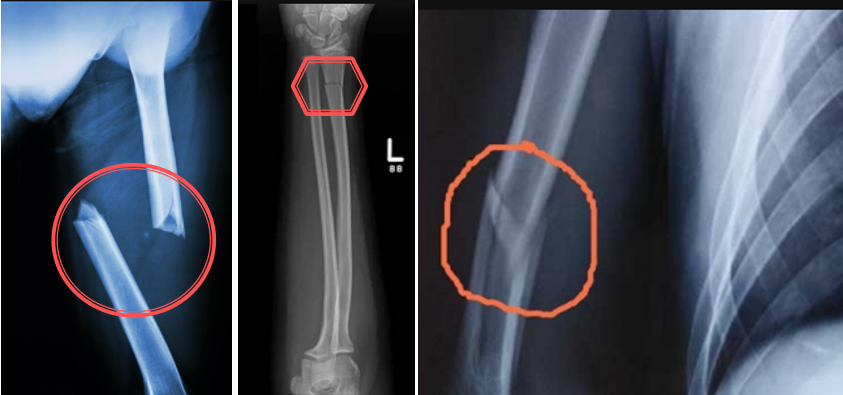

按照骨的完整性可分为:

1)完全性骨折:骨的完整性和连续性全部破坏或中断,骨断裂成三块以上的碎块成为粉粹性骨折。

2)不完全骨折:骨未完全断裂,仅部分骨质破裂,如裂缝、凹陷、青枝骨质

3)嵌顿性骨折:断骨两端互相嵌在一起